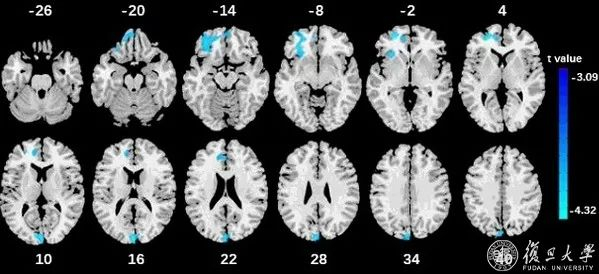

类脑研究院团队通过青少年脑影像学随访队列分析揭示多动症双通路模型的关键脑区

前额叶和枕叶区的灰质体积越小多动症症状越严重

近日,复旦大学类脑智能科学与技术研究院院长冯建峰教授、罗强副研究员团队,与英国剑桥大学、伦敦国王学院等单位合作,研究青少年中注意缺陷多动障碍双通路模型的神经基础,发现左楔叶结构不仅和多动症的认知和动机功能受损相关,还与多动症的遗传风险相关,并且可以预测2年后的多动症症状,很可能提供了多动症的一种影像学标记物。5月7日,这一研究成果以《青少年中多动症双通路模型的神经基础》为题在线发表于《美国精神病学杂志》(The American journal of psychiatry)。

该研究表明,多动症的双通路模型同时存在分离的和共同的脑结构基础。左侧枕叶灰质体积和多动症症状相关,和认知与动机两条通路的受损情况相关,和多动症遗传风险相关,对多动症的症状具有预测性,并且与多动症药物治疗紧密相关。据冯建峰介绍,该研究的发现或有助于构建多动症的影像学标记,帮助精确诊断和疗效评估。